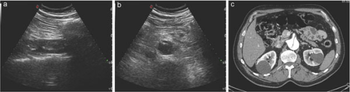

Normal

Abnormal

Abdominal Aortic Aneurysm

Aortic Dissection